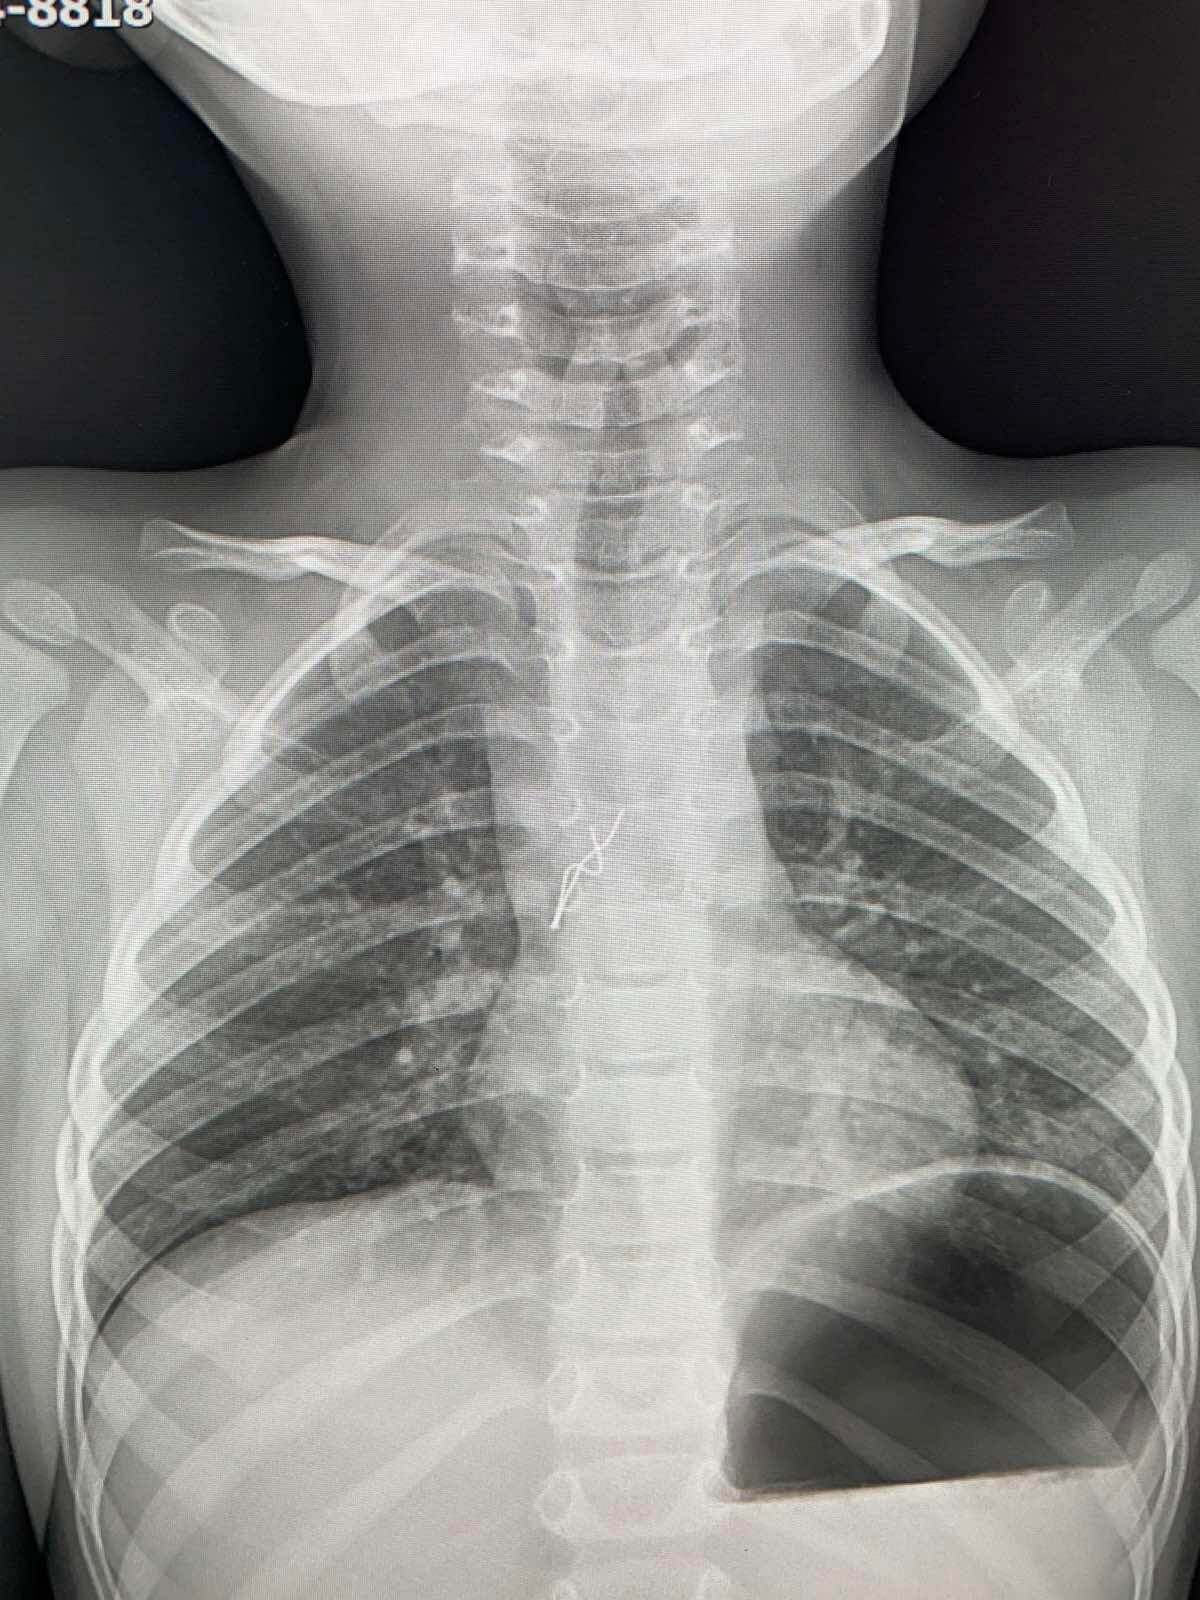

Родители рассказали, что ребенок начал кашлять и задыхаться. Родители сразу вызвали скорую. В больнице сделали рентген и обнаружили инородный предмет.

Торакальный хирург Александр Колодий рассказал, что ему удалось достать лампочку без хирургического вмешательства.

По словам врача, ее усики повредили слизистую оболочку в участке бифуркации трахеи и там появились мелкие кровоизлияния.

"Я схватил усики щипцами, завел их в тубус бронхоскопа и вместе с ним достал лампочку из бронхов ребенка", – сказал Колодий.